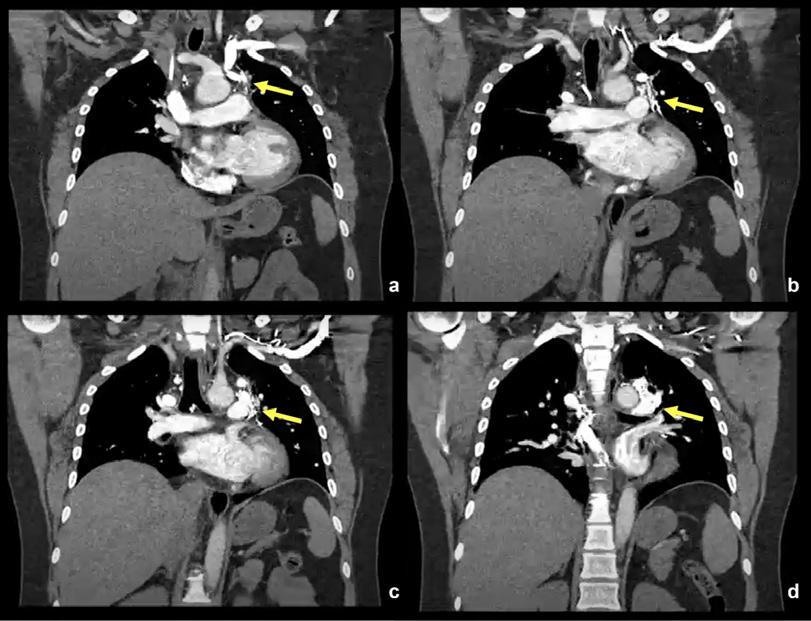

Se decidió realizar Angiotac: No impresiona TEP. Se destaca defecto de relleno en porción proximal de vena cava superior

sugestiva de trombosis, posterior al extremo distal del catéter de infusión (Fig. 3).

Se detectó también circulación colateral hiliar bilateral con drenaje en sistema ácigos mayor y menor (Fig. 4, 5 y 6). Se inició tratamiento con rivaroxabán (antitrombótico) y manejo clínico de la paciente.

Figura 3. Angiotac: En las imágenes a, b, c y d se identifica ausencia de opacificación con el contraste de la Vena Cava Superior, con presencia catéter en su interior, hallazgos sugestivos de trombosis probablemente relacionados al cateterismo central realizado.

Figura 4. En las imágenes a, b, c y d, se identifica sistema de vena ácigos dilatado y prominente. En la imagen d, plano coronal donde se identifica al sistema hemiácigos desembocando al sistema ácigos a la altura de la 7ma vértebra dorsal, donde cruza el plano medial y se lateraliza hacia la región paravertebral derecha.

Figura 5. Obsérvese la desembocadura de la vena ácigos superior en la aurícula derecha.

Figura 6. En las imágenes

d

la

colaterales del sistema

izquierda,